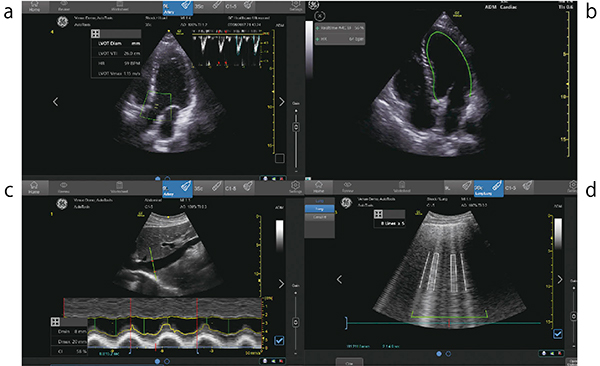

Venueシリーズのautomated toolは,AIを駆使し,検者は指定の部位をスキャンしボタンを1回押すだけで,さまざまな計測値を得ることができる。現在,Venueシリーズは,4つのautomated toolがオプションとして搭載できる(図2)。

図2 Automated tool

a:Automated VTI b:Real-Time EF

c:Automated IVC d:Automated B-line

・Automated VTI:心尖部長軸像もしくは心尖部五腔像を描出し,ワンタッチで左室流出路の速度時間積分値(VTI)を算出する。

・Real-Time EF:心尖部四腔像を描出し,ワンタッチで左室駆出率をリアルタイムで算出する。従来の当社超音波診断装置では,2D speckle tracking技術を応用し保存した画像から駆出率(以下,EF)を算出していたが,Real-Time EFはAI技術の活用により,スキャンをしている際に心拍ごとにEF値が表示される。

・ Automated IVC:下大静脈の長軸を描出し,ワンタッチで下大静脈の呼吸性変動CI値を算出する。自発呼吸と人工呼吸,それぞれに対応した計測が可能である。

・Automated B-line:胸部肋間にプローブを当て,ワンタッチでその肋間のB-lineのカウントを行う。